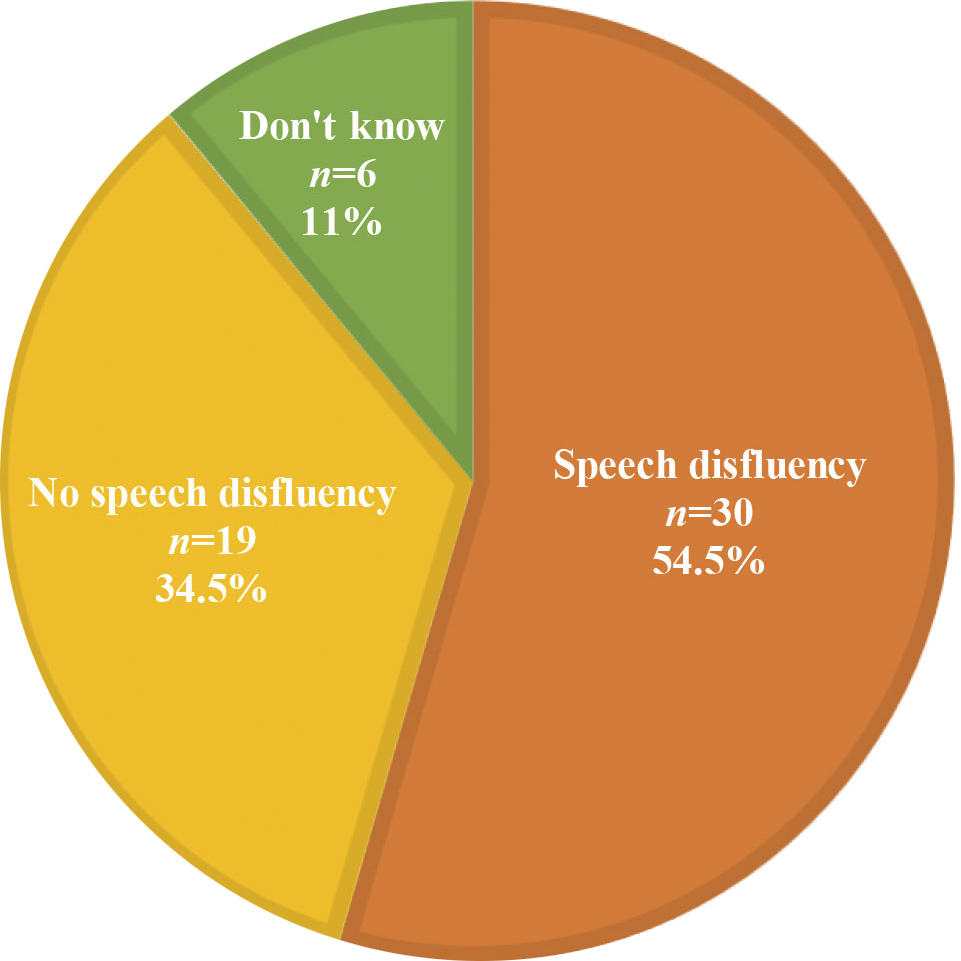

Vi måste prata om klimakteriet.

Vi måste prata om klimakteriet – igen.